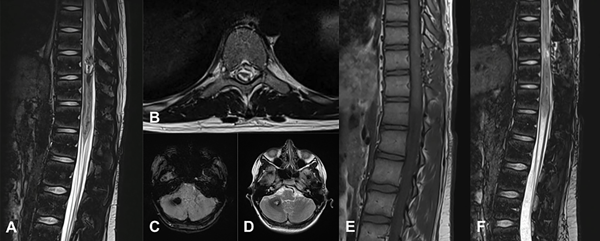

Figura 6. MC medular a nivel T10. Paciente masculino de 15 años que ingresa por paraplejía progresiva de varios días de evolución y compromiso de esfínteres. A) RM de columna dorsolumbar corte sagital T2-STIR que evidencia lesión heterogénea, compatible con MC. B) RM corte axial T2-STIR. C-D) RM de cerebro secuencias SWI y T2 que muestra otra lesión en hemisferio cerebeloso derecho. Por la severidad del cuadro clínico se realizó cirugía de urgencia. E-F) RM de columna dorsolumbar postquirúrgica, secuencias T1 y T2-STIR donde se observa el lecho quirúrgico libre de lesión. Se observa laminectomía del nivel T10. El paciente tuvo una recuperación parcial del foco neurológico. Actualmente en rehabilitación.